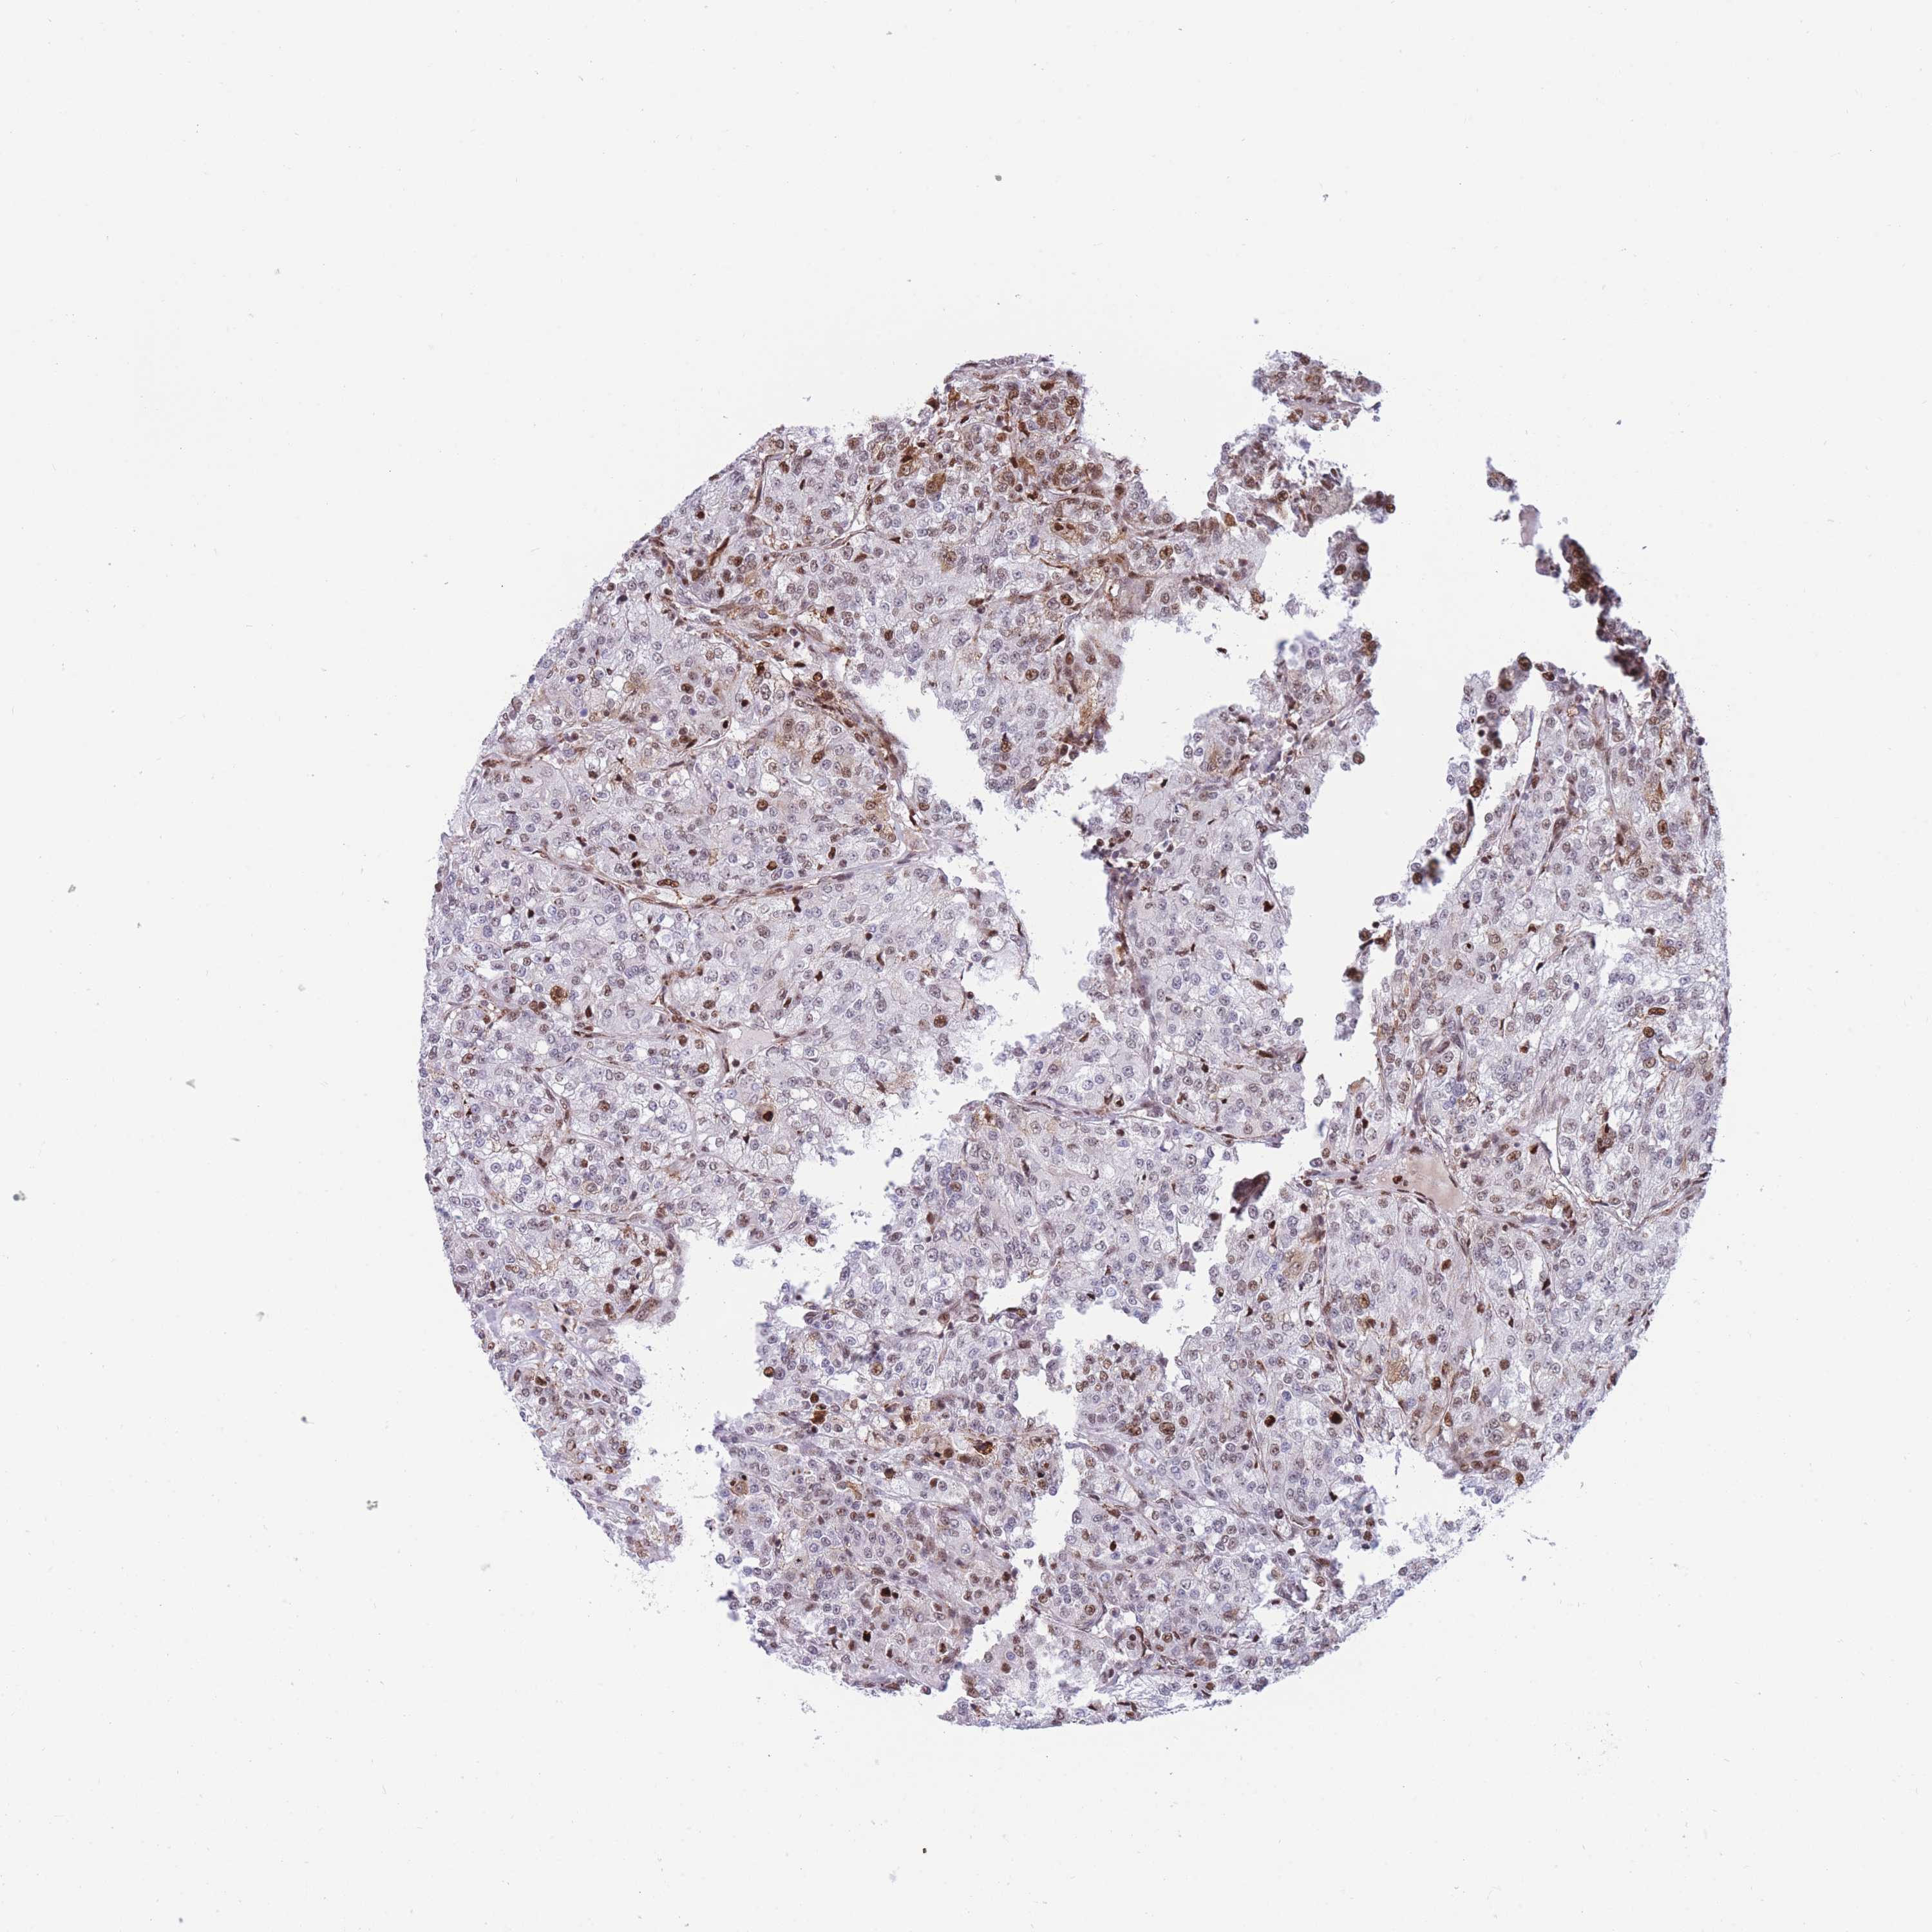

KIDNEY RENAL PAPILLARY CELL CARCINOMA (TCGA) - Interactive survival scatter ploti

The Survival Scatter plot shows the clinical status (i.e. dead or alive) for all individuals in the patient cohort, based on the same data that underlies the corresponding Kaplan-Meier plots. Patients that are alive at last time for follow-up are shown in blue and patients who have died during the study are shown in red.

The x-axis shows the expression levels (FPKM) of the investigated gene in the tumor tissue at the time of diagnosis. The y-axis shows the follow-up time after diagnosis (years). Both axes are complimented with kernel density curves demonstrating the data density over the axes. The top density plot shows the expression levels (FPKM) distribution among dead (red) and alive patients (blue). The right density plot shows the data density of the survived years of dead patients with high and low expression levels respectively, stratified using the cutoff indicated by the vertical dashed line through the Survival Scatter plot. This cutoff is automatically defined based on the FPKM cutoff that minimizes the p-score. The cutoff can be changed by dragging the vertical line or by entering a cutoff value in the square labeled "Current cut-off".

Under the Survival Scatter plot the p-score landscape (black curve; left axis) is shown together with dead median separation (red curve; right axis). Dead median separation is the difference in median mRNA expression between patients who have died with high and low expression, respectively. It is calculated as follows: median FPKM expression of dead patients with high expression - median FPKM expression of dead patients with low expression. This is intended to aid the user in visually exploring custom cutoffs and the associated p-scores and dead median separation.

Individual patient data is displayed and can be filtered by clicking on one or more of the category buttons on the top of the page. Categories describing expression level and patient information include: high, low, alive, dead, female, male and tumor stages. The scale of the x-axis can be toggled between linear and log-scale by clicking on the "x log" button. Mouse-over function shows TCGA ID, patient information and mRNA expression (FPKM) for each patient.

& Survival analysisi

Kaplan-Meier plots summarize results from analysis of correlation between mRNA expression level and patient survival. Patients were divided based on level of expression into one of the two groups "low" (under cut off) or "high" (over cut off). X-axis shows time for survival (years) and y-axis shows the probability of survival, where 1.0 corresponds to 100 percent.

DNAJC3 is not prognostic in Kidney Renal Papillary Cell Carcinoma (TCGA)